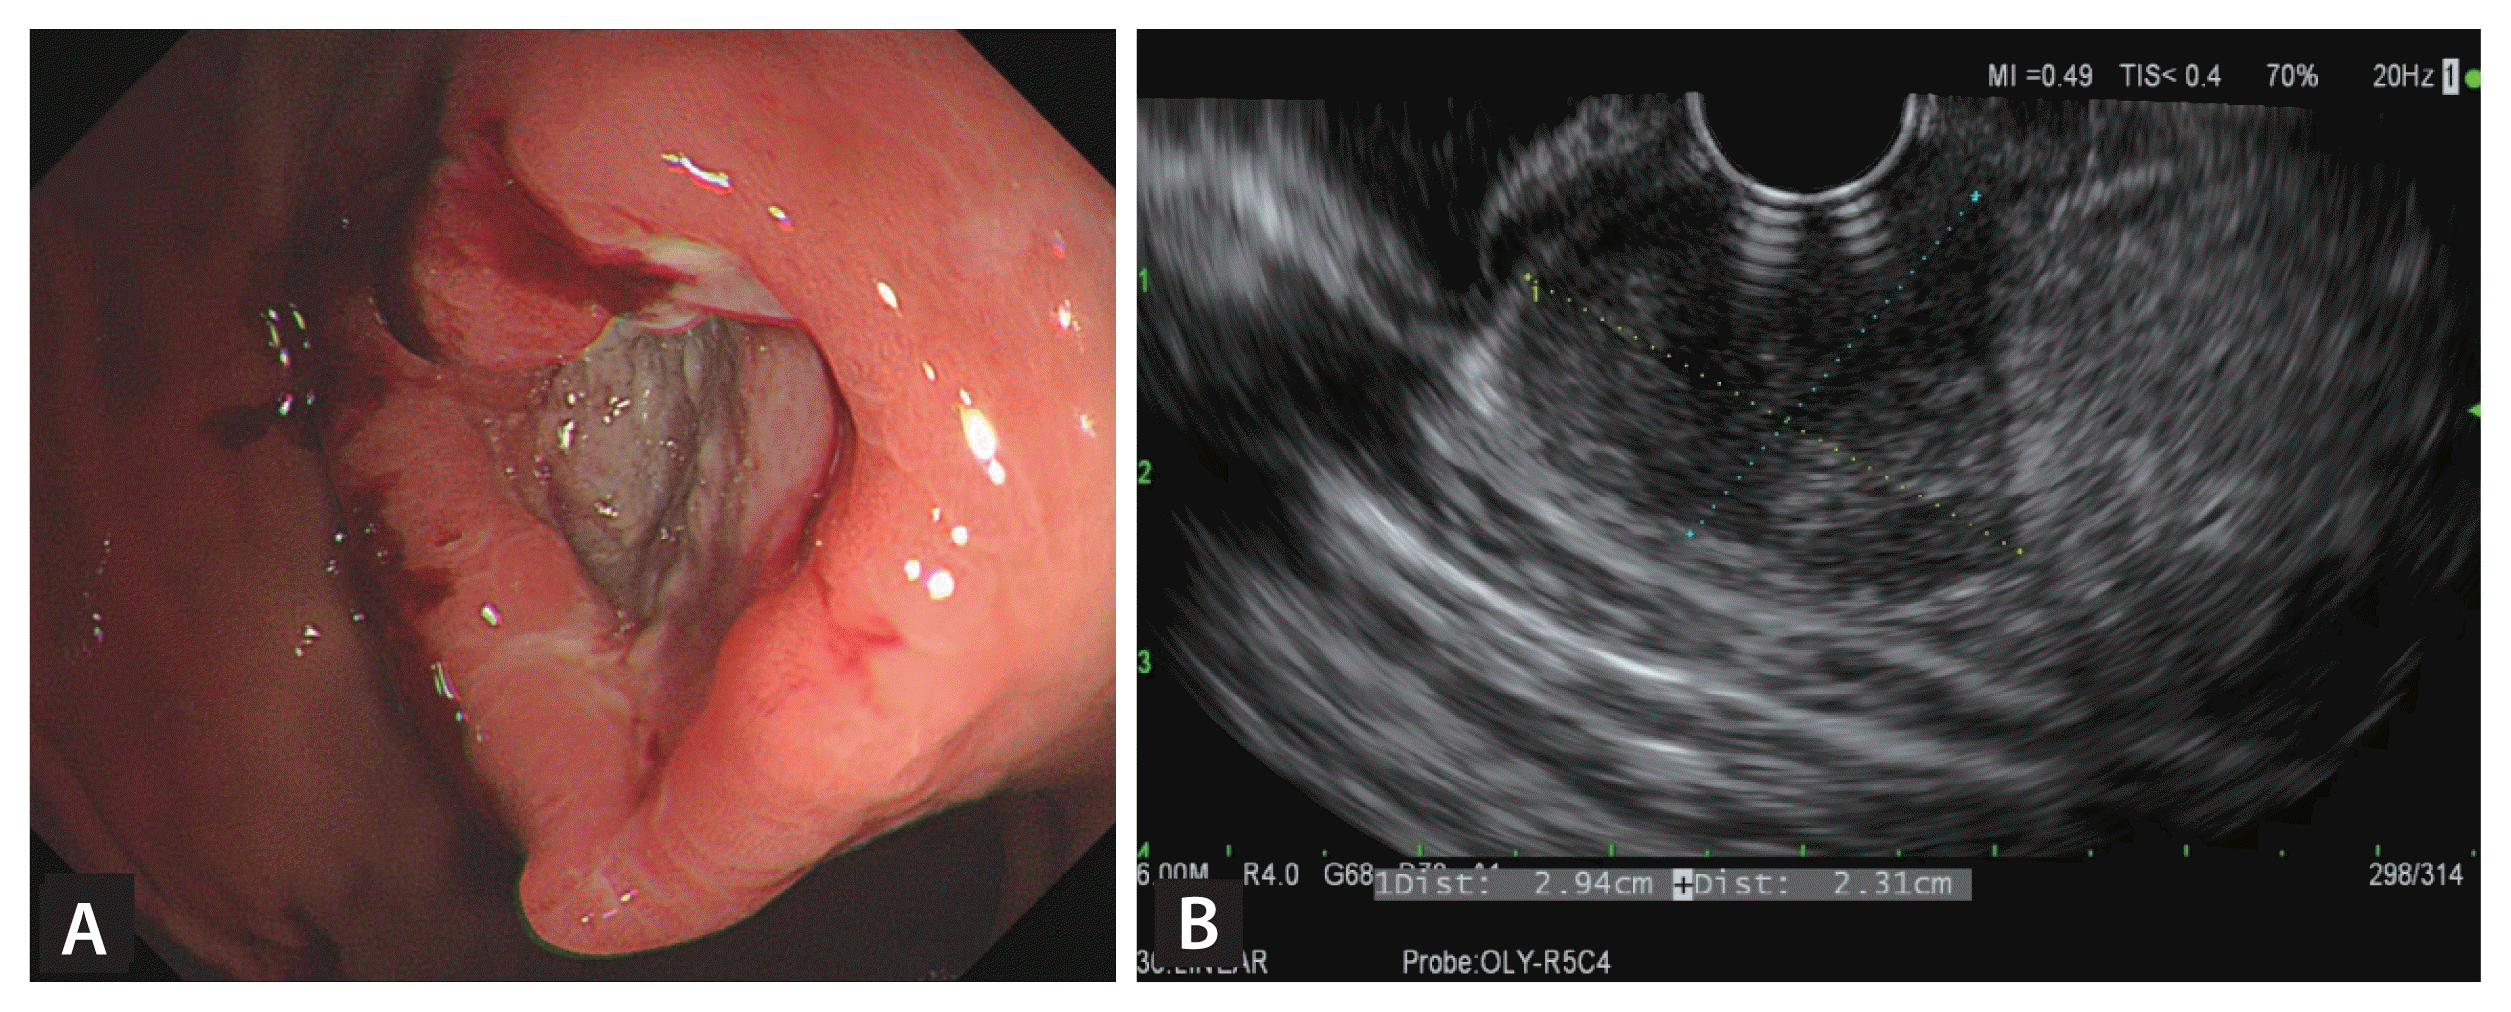

A 27-year-old man presented with severe upper abdominal pain for 3 weeks. It was aggravated after meal. He was diagnosed with tuberculous pleurisy 2 months ago, and receiving the standard 6-month anti-tuberculosis medications including isoniazid, rifampicin, ethambutol, and pyrazinamide. He had not taken nonsteroidal anti-inflammatory drugs or aspirin during the follow-up period and pain control was done using acetaminophen. Abdominopelvic computed tomography (CT) revealed a 3-cm round gastric mass with central ulceration in the upper body, which were not prominent in the previous CT scan 2 months ago. Upper endoscopy revealed 3 cm-sized subepithelial mass with an ill-defined central ulceration on the midbody (Fig. 1A). Endoscopic ultrasound (EUS) revealed a heterogenous hypoechoic mass and central hyperechoic foci (Fig. 1B). Forceps biopsy and fine needle aspiration biopsy (FNAB) were performed without complications. The histologic diagnosis was chronic granulomatous inflammation with ulceration, consistent with tuberculosis (Fig. 2A). Although tissue culture and polymerase chain reaction was negative for tuberculosis, the final diagnosis was a paradoxical reaction of tuberculosis. Thus he continued to receive anti-tuberculosis medications as scheduled. Then upper gastrointestinal symptom gradually improved without additional complication. Follow-up endoscopy and CT scan after 3 months later revealed complete resolution of the gastric mass (Fig. 2B). Informed consent was obtained from the patient.

Figure 1

(A) Upper endoscopy images showed a 3-cm sized gastric mass with irregular-margined ulcer. (B) Endoscopic ultrasound imaged showed a heterogenous hypoechoic mass with central hyperechoic foci.